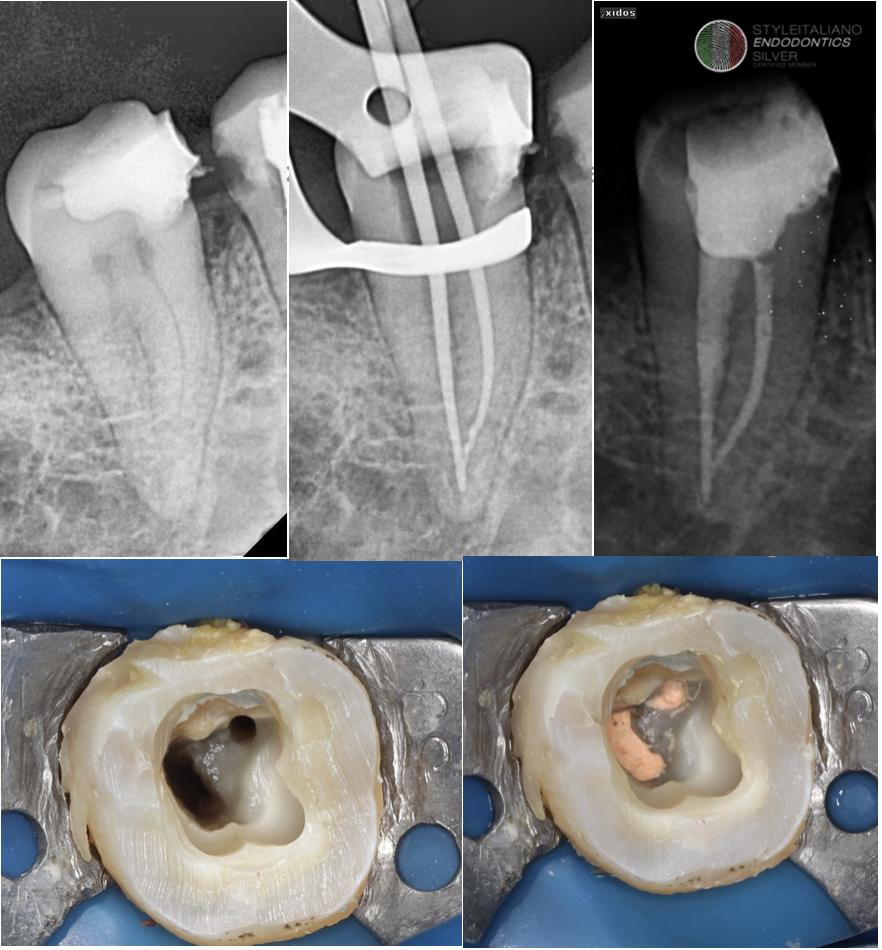

Fig. 2

C-shaped root canal systems exhibit significant anatomical complexity and variability. Several classification systems have been proposed to describe their morphology. The most widely accepted and clinically relevant classification is that of Fan et al. that was done in 2004, which categorizes C-shaped canals according to their cross-sectional configuration.

In the next slides I’m gonna share with you every type clinically & radiographically

Fan's Classification

Type Description

C1

A continuous C-shaped canal with no separation.

C2

A semicolon-shaped canal resulting from discontinuation of the C outline.

С3

Two or three distinct canals with no C-shaped configuration. • C3a: Two separate canals. • C3b: Three separate canals.

C4

A single round or oval canal.

C5

No visible canal lumen (often observed near the apex).